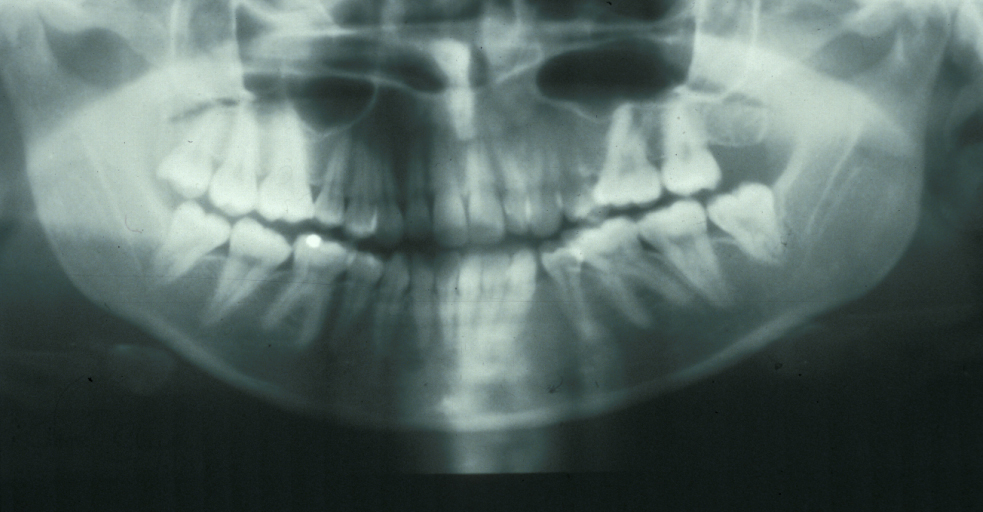

Assessment of the tooth is both clinical and radiographic. If somebody presents in pain, it is important to establish that this is coming from the third molar and not elsewhere. Pain is often vague, poorly localised and may be referred from another tooth, or as part of facial arthromyalgia (condition affecting the jaw joint). A dental panoramic radiograph is ideal as it helps to assess all the teeth at once. The health of the adjacent molars may influence the decision whether to remove the third molar or not. Large crowns or old restorations are all at risk of dislodgement during surgery. It is also worth considering whether alternative treatment options are available. For instance, pericoronitis due to an over-erupted upper third molar may be dealt with by extracting that tooth only, with or without operculectomy. In the presence of other teeth of poor prognosis, will it be better in the long term to save the third molar which may be used as a denture or bridge abutment in the future?

These points help to determine whether the tooth can be simply elevated or will need a surgical approach. A series of radiographs depicted in Figure 4 to Figure 8 illustrate these points further.